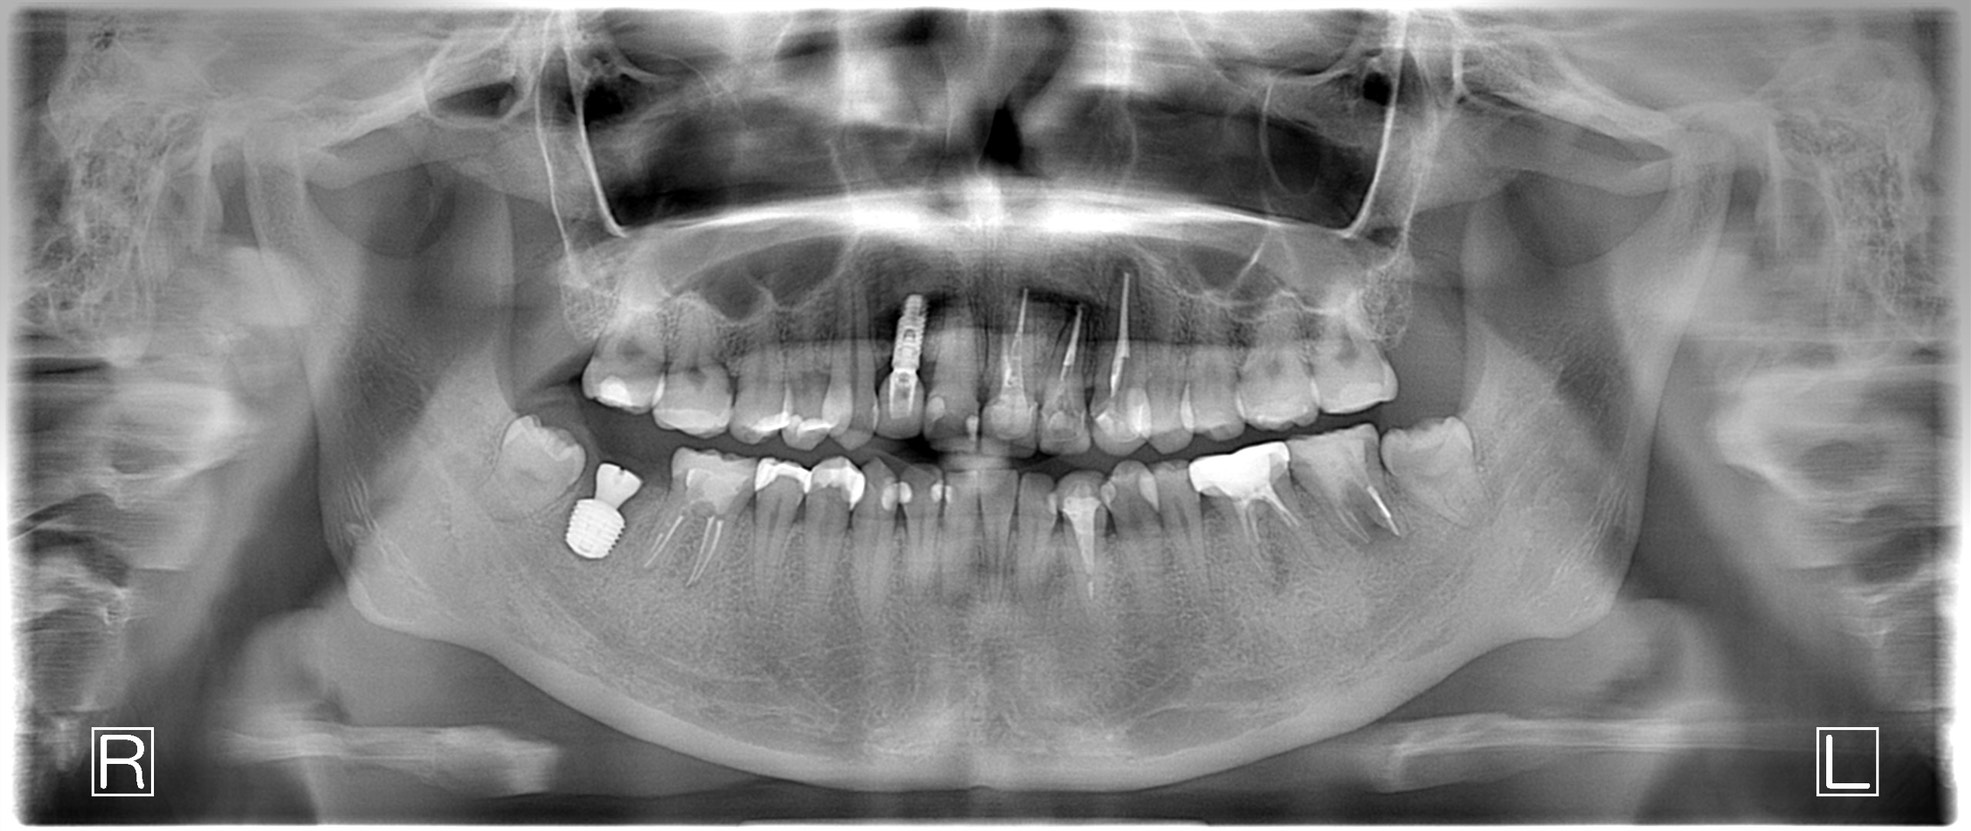

| 診断結果 | 右下7番歯根破折 |

| 治療内容 | 抜歯即時インプラント |

| 治療期間 | 8週間 |